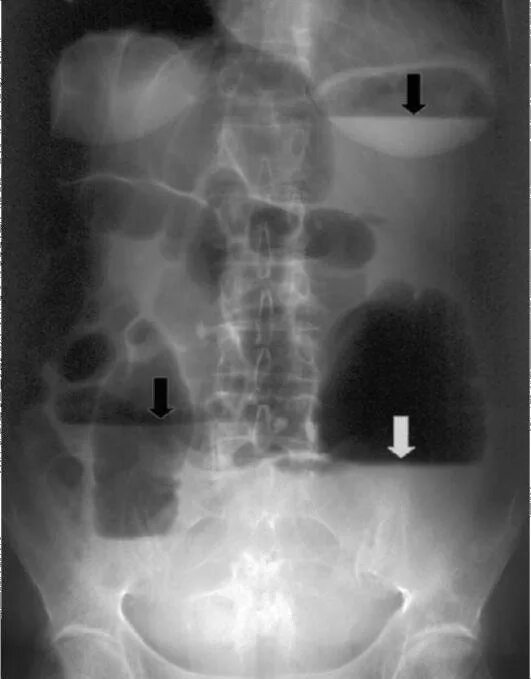

Симптом чаши